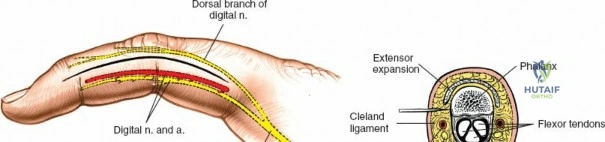

The digital neurovascular bundles (NVBs) run along the radial and ulnar sides of each digit, volar to the collateral ligaments, providing sensation and vascularity. Proper identification and protection of these bundles are paramount during any volar dissection. Proximally, the median nerve gives rise to recurrent motor branches to the thenar muscles and sensory branches to the thumb, index, middle, and radial half of the ring finger. The ulnar nerve supplies the hypothenar muscles, adductor pollicis, and interossei, along with sensory innervation to the little finger and ulnar half of the ring finger. The palmar arches (superficial and deep) provide critical vascular supply to the hand.

Surface landmarks guide the incision. In the digits, these include the distal phalangeal crease (just proximal to the distal interphalangeal joint), the proximal interphalangeal crease, and the metacarpophalangeal crease. In the palm, the distal palmar crease and thenar/hypothenar creases are important.

The skin incision must provide adequate exposure without creating straight lines across joint creases, which can lead to scar contracture. The Bruner zigzag incision is the standard for digital access due to its excellent exposure and prevention of flexion contractures. It incorporates the natural creases and extends proximally and distally in a zigzag fashion along the length of the digit. The apices of the V's are typically located over the mobile skin of the phalanges, avoiding the fixed skin over the joint creases.

- Finger Incision (Bruner): Begins dorsally/mid-laterally over the distal phalanx, angles volarly, crosses the volar skin crease, then angles back to the mid-lateral line, avoiding straight lines across joints. This allows creation of triangular skin flaps.

After marking the incision, the skin and subcutaneous tissues are carefully incised. In the digits, the triangular skin flaps created by the Bruner incision are elevated using fine skin hooks or small self-retaining retractors. Dissection should proceed in the subcutaneous plane, superficial to the digital neurovascular bundles, which run along the radial and ulnar borders of the digit, immediately adjacent to the flexor sheath.

Care must be taken to identify and protect these bundles. Any existing lacerations or hematomas are debrided. The digital nerves and vessels are carefully dissected free from the surrounding connective tissue and retracted, typically dorsally and laterally, using vessel loops or fine retractors to provide clear access to the underlying flexor sheath.